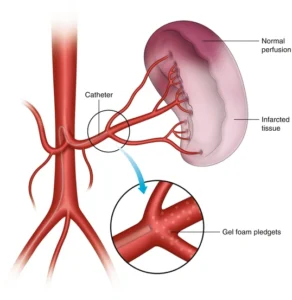

Splenic Artery Embolization

What is Splenic Artery Embolization?

Splenic artery embolization is a procedure that reduces blood flow to the spleen by blocking a portion of the splenic artery. It is commonly performed to manage complications related to liver disease and portal hypertension.

Conditions Treated

Hypersplenism (overactive spleen)

Portal hypertension complications

Trauma-related splenic bleeding

Certain blood disorders

Benefits

Minimally invasive treatment

Preserves spleen function

Reduced bleeding risk

Shorter recovery period